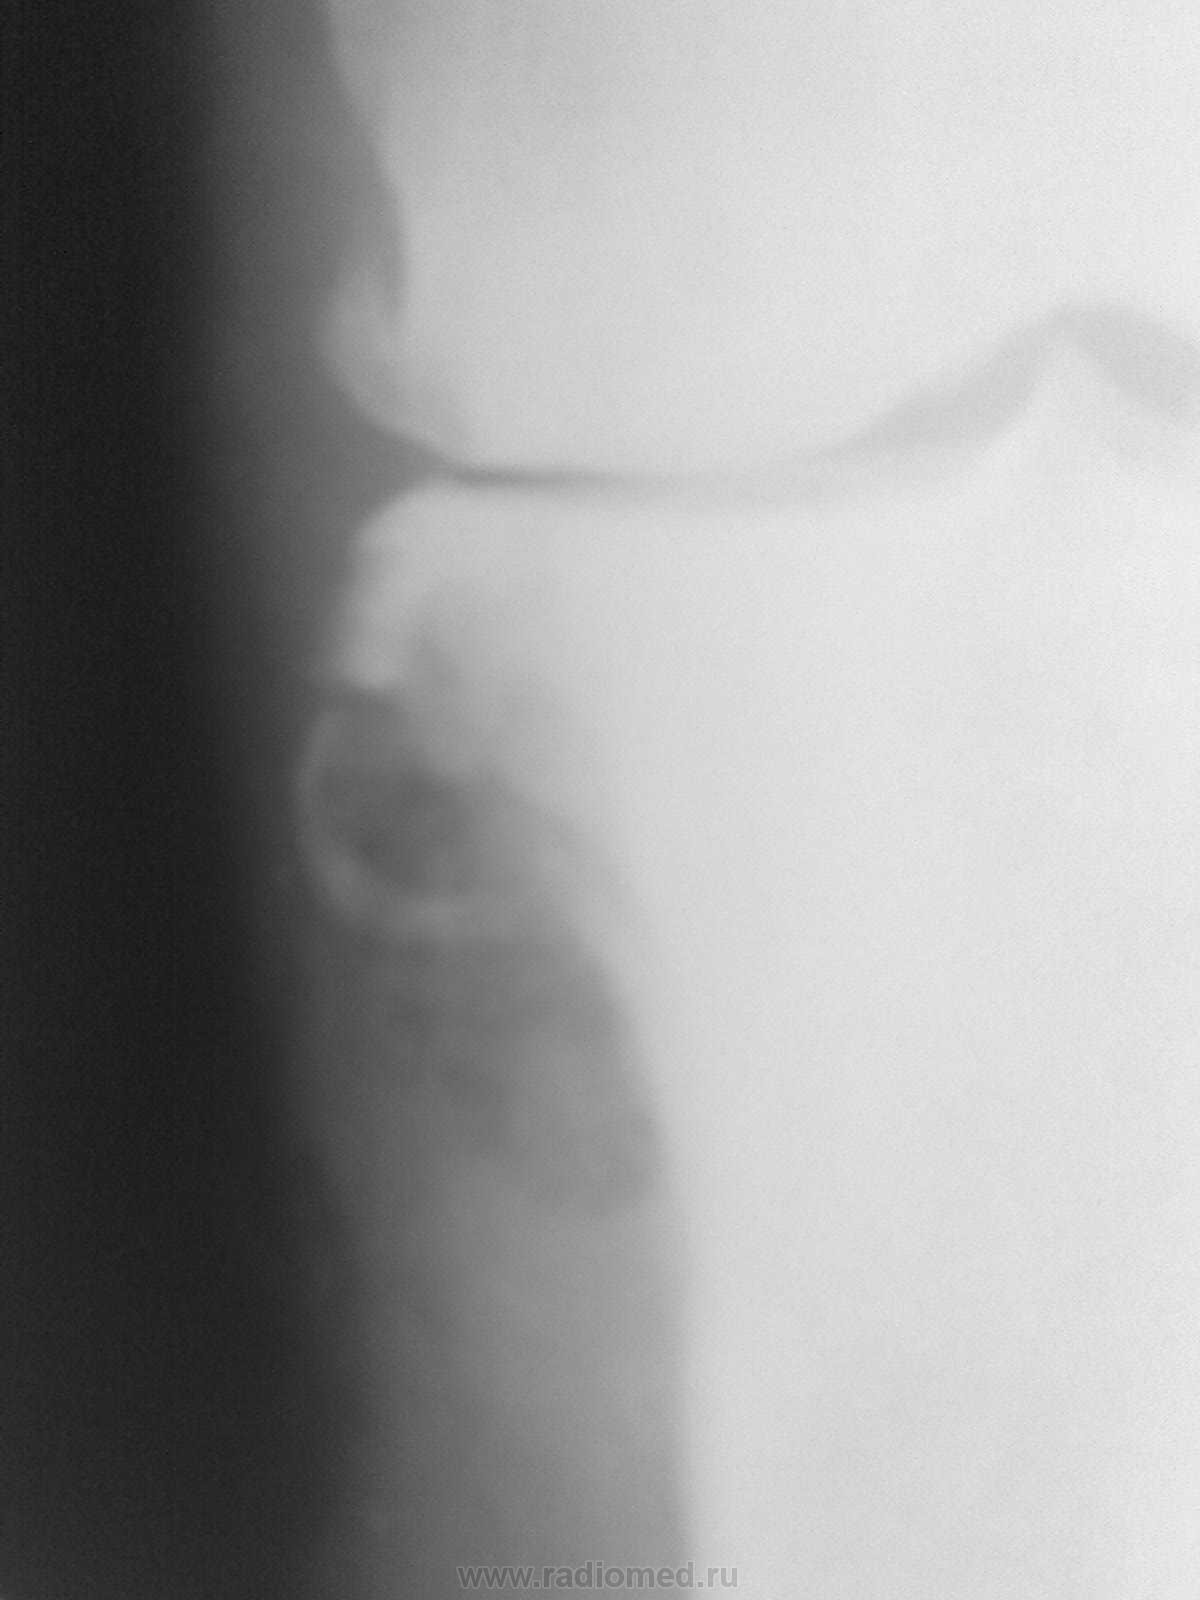

Пациентка жалуется на боль в обл. внутр. мыщелка б.берц кости. Снимки мерзкого качества, но это все, что есть, временной интервал - около года (9 - 10 гг). Прилагаю КТ на пленке. Наша версия - периостальная липома (ангиолипома, миксома).  Публикую не только как интересный случай, но и для консультации. Аналогичное сообщение размещено на радиографии.